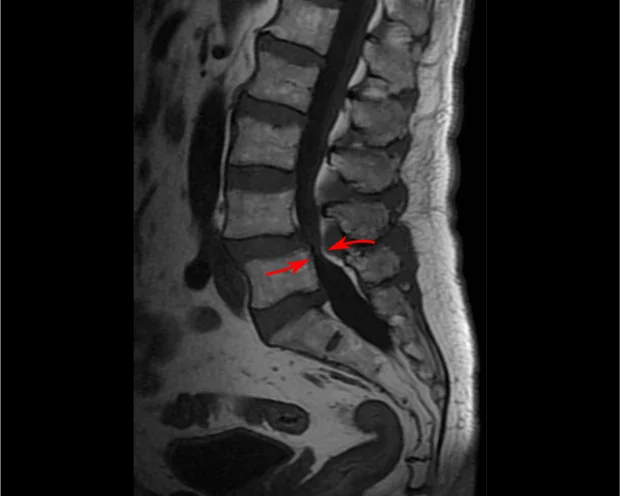

Диагнозата на спинална стеноза включва пълна оценка на състоянието на гръбначния стълб и неврологичната функция. Обикновено се започва със сваляне на подробна анамнеза (разпит) и физикален преглед. За откриване на изменения в гръбначния стълб и определяне на степента и местоположението на стенозата се изпулват образни изследнвания като рентгенография, компютърна томография, миелография, ЯМР(ядрено-магнитен резонанс).

- Ядрено-магнитен резонанс (ЯМР) - Дава подробна информация за гръбначния канал и нервните структури.